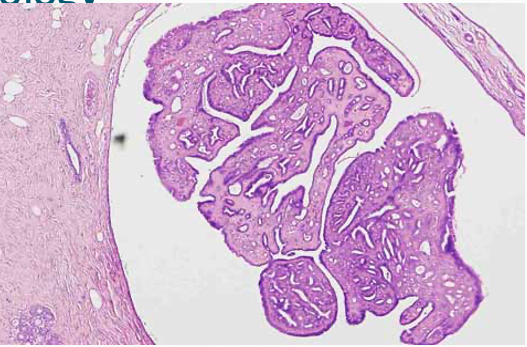

22

Q

What is this?

A

Intraductal papilloma - histology. Large ducts which is being dilated. Capillaries within them.

How well did you know this?